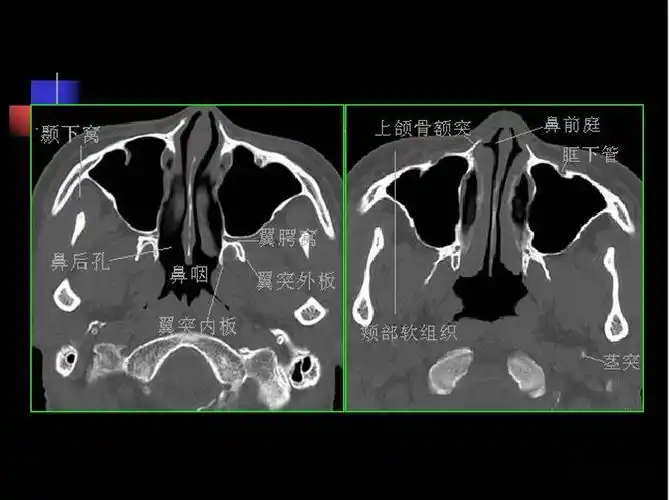

鼻骨解剖与骨折的ct表现ppt

写鼻骨骨折ct报告,一定要了解的解剖

收藏必备鼻咽部的ct详细解剖

鼻及鼻窦影像解剖及相关疾病影像诊断